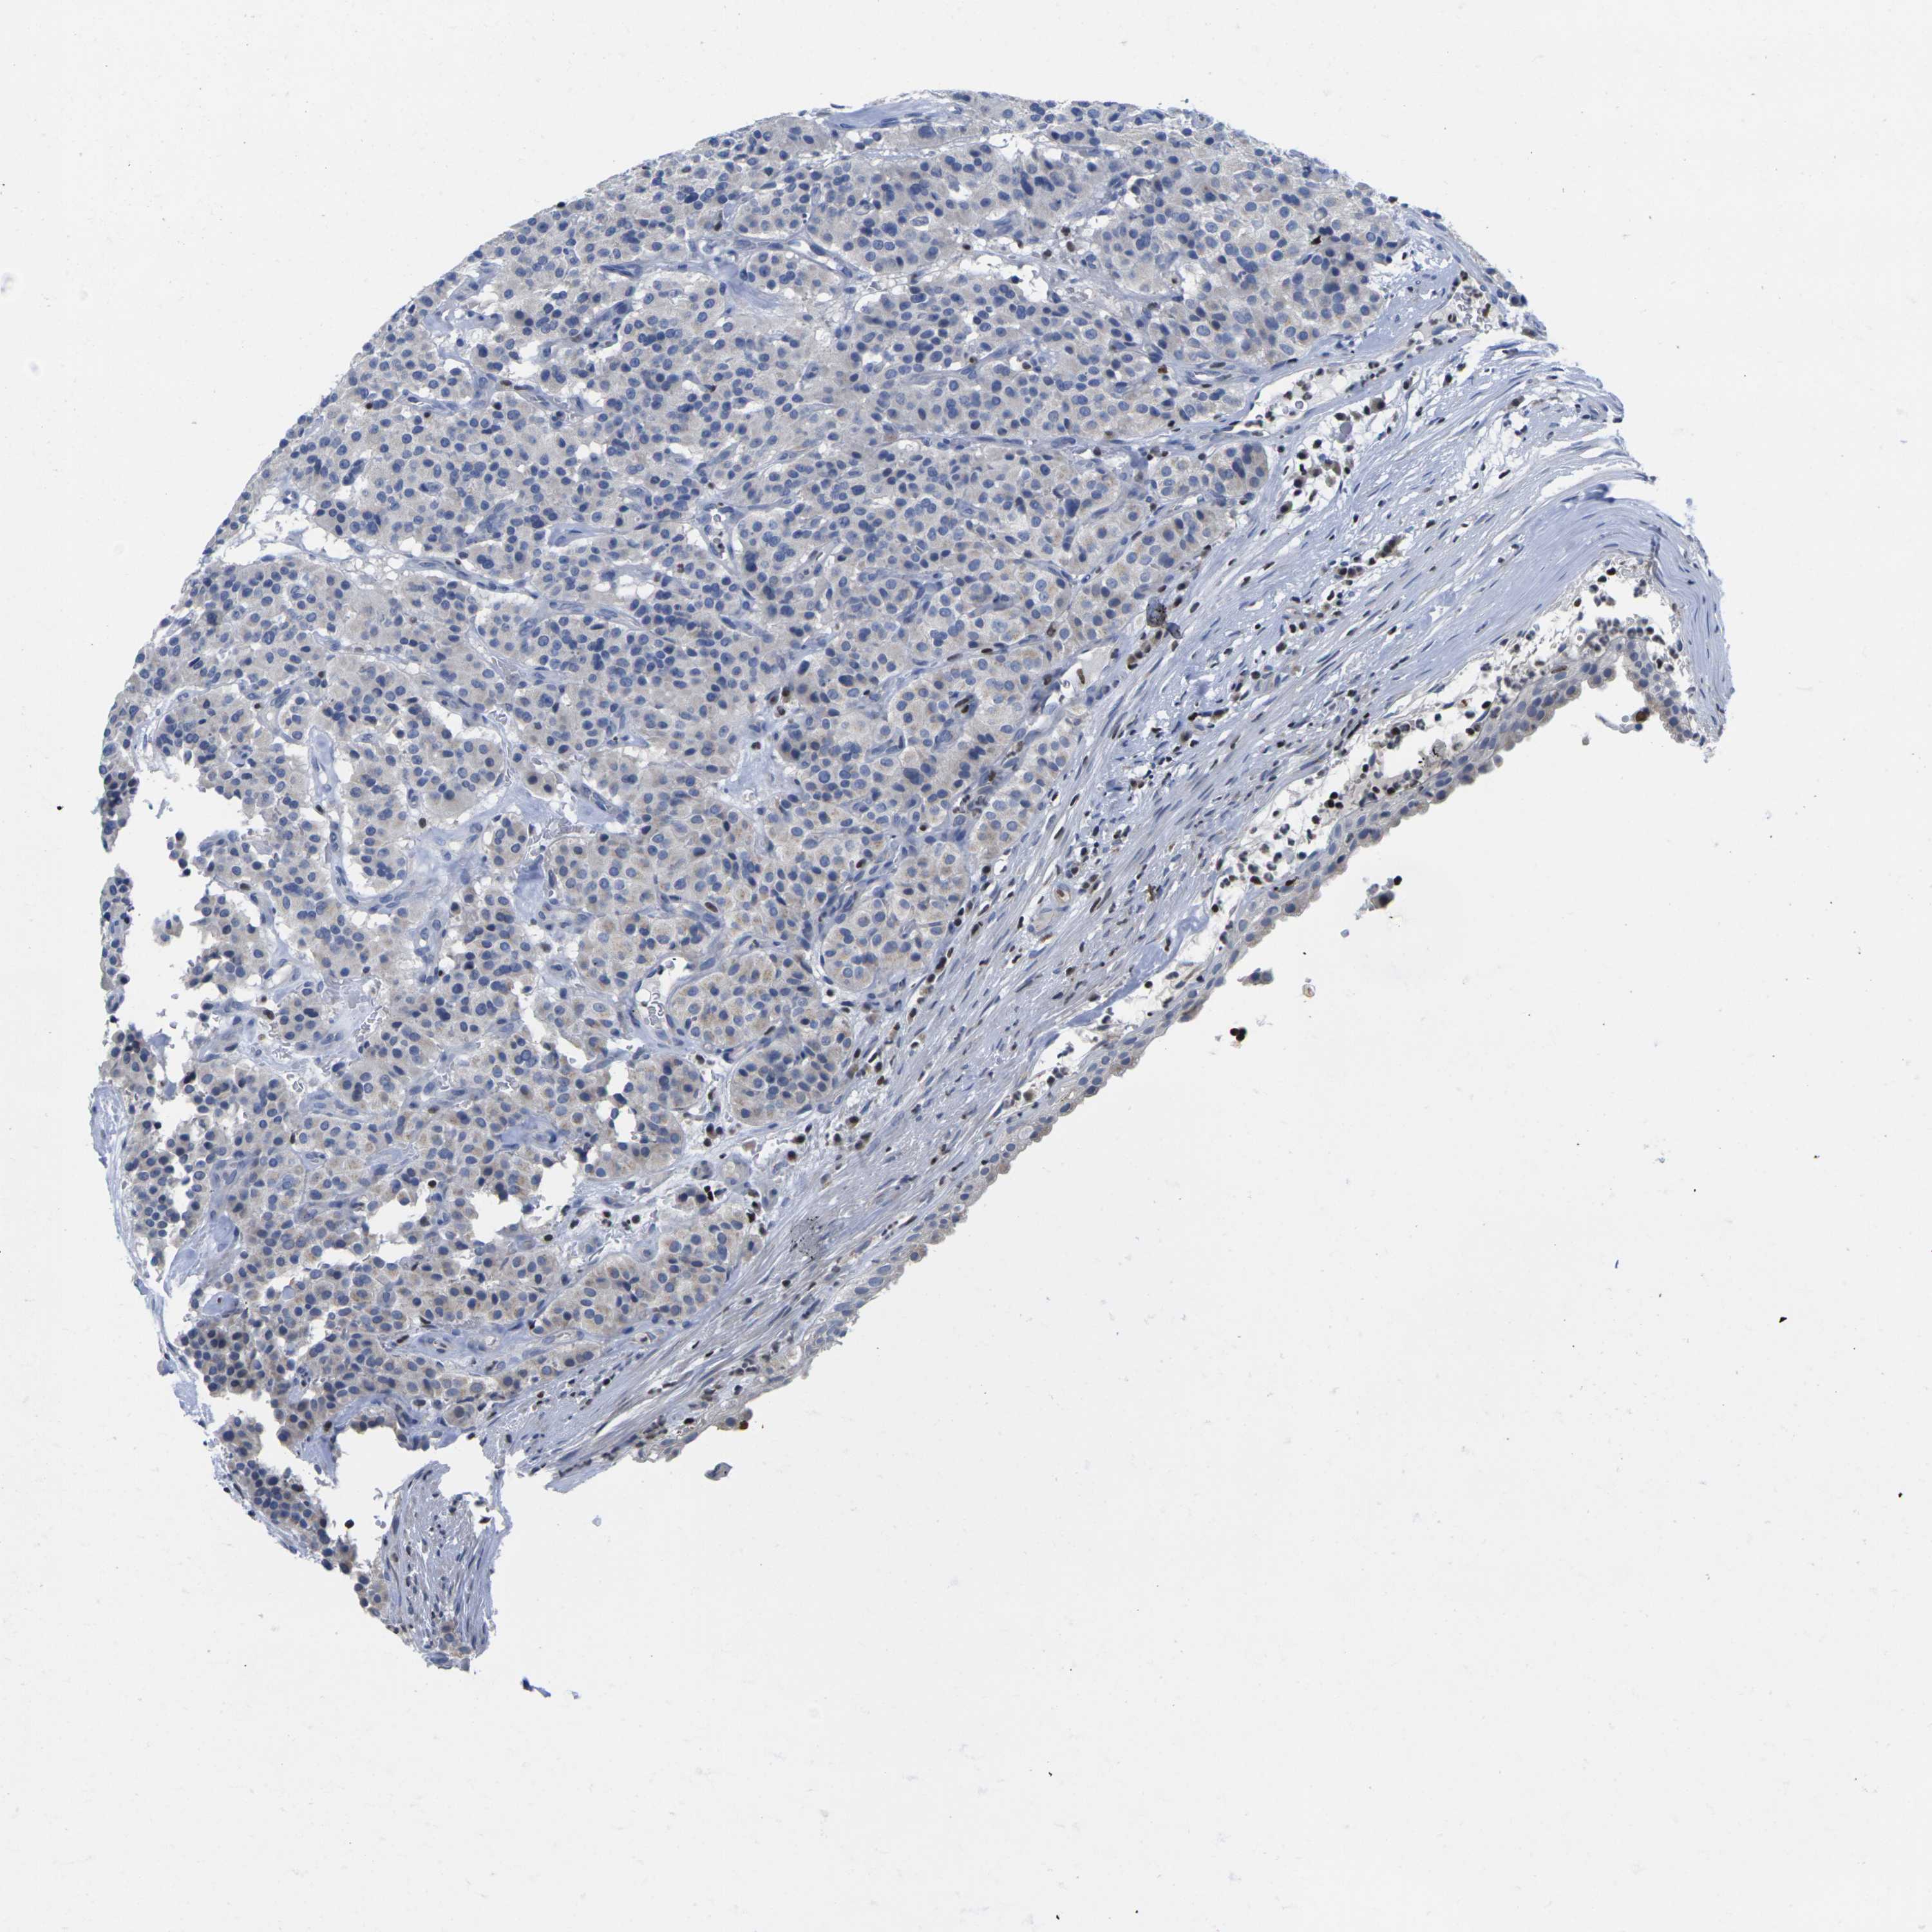

CARCINOID - Protein expressioni

A mouse-over function shows sample information and annotation data. Click on an image to view it in a full screen mode. Samples can be filtered based on level of antibody staining by selecting one or several of the following categories: high, medium, low and not detected. The assay and annotation is described here.

Each image is clickable and will lead to virtual microscopy that enables deeper exploration of all samples and also displays staining intensity scores, fraction scores and subcellular localization as well as patient and tissue information for each sample.

Antibody HPA035222

Carcinoid, malignant, NOS